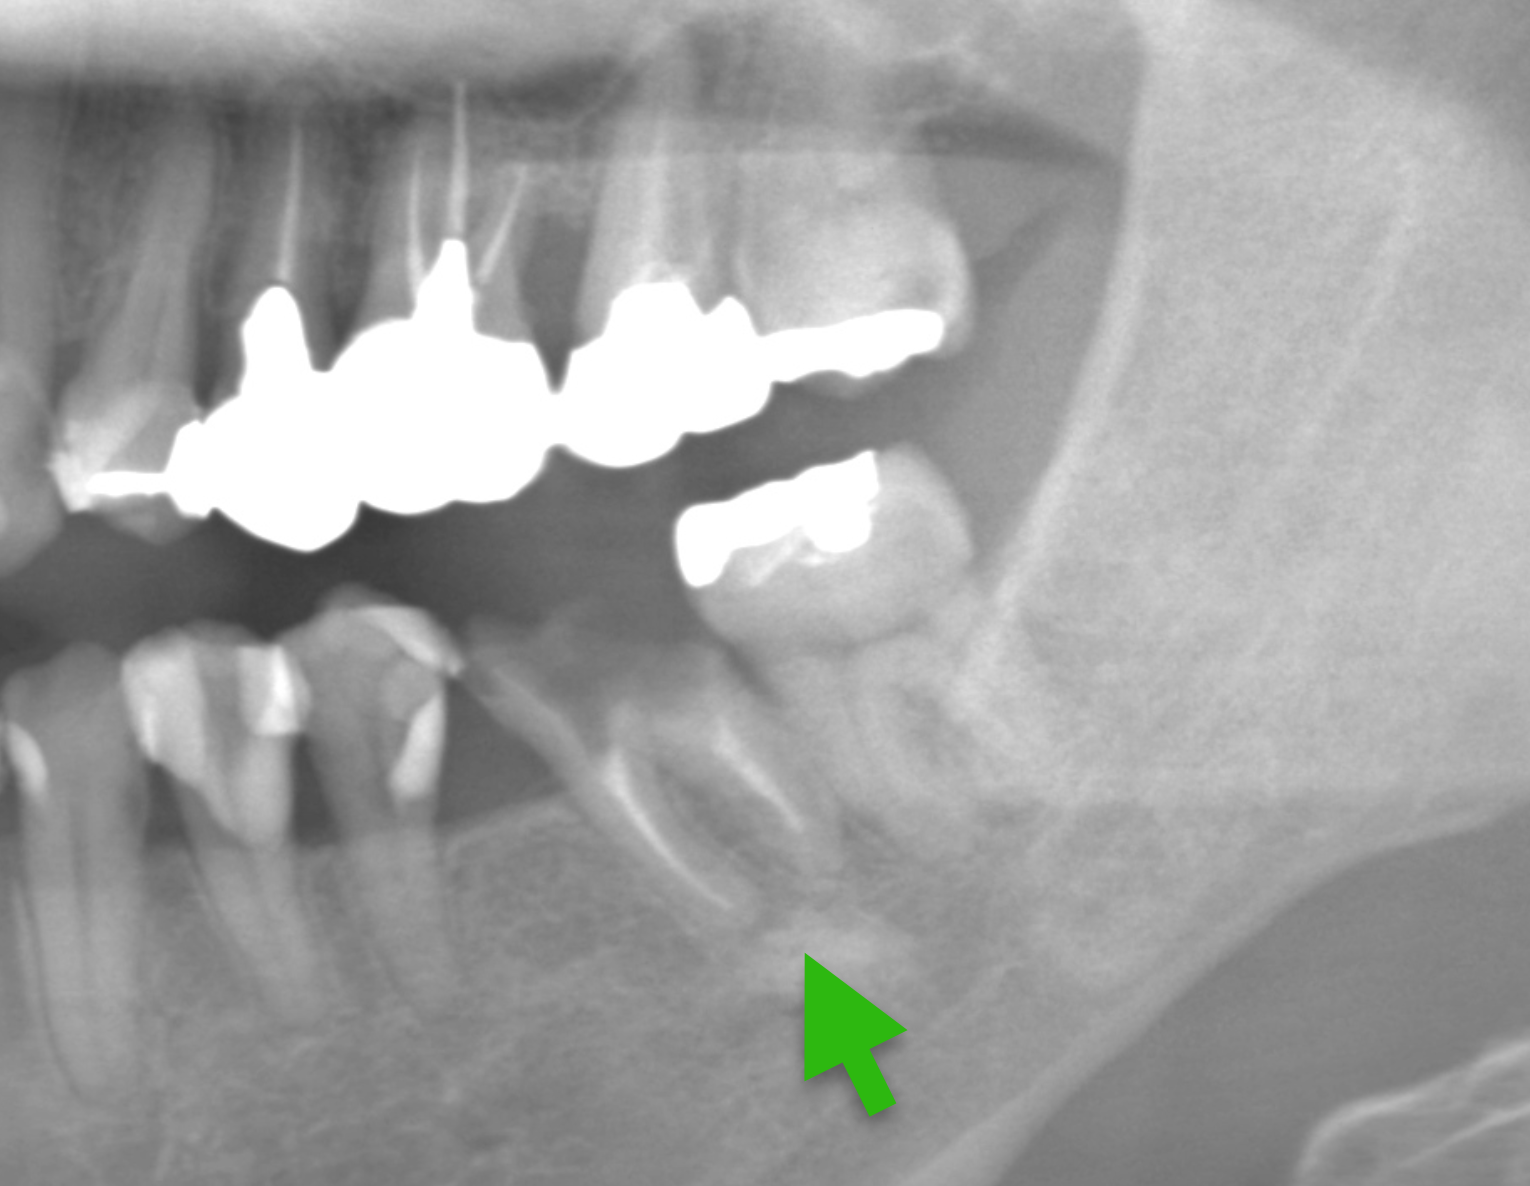

Case15.

| 主 訴 | 左右の奥歯がグラグラする、食事しづらい |

| 治療期間 | 約6ヶ月 |

| 治療費 | インプラント3本、被せ物4本の合計: 1,551,000円(税込) |

| 治療内容 | 歯が割れている部分を抜歯し、歯が欠損している部分を インプラントで治療し奥歯での噛み合わせを 作りました。 |

| 治療のリスク | インプラントの手術の後は腫れ、痛みが出ることが あります。抜歯後は腫れることがあります。 |